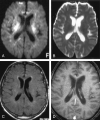

F<sc>ig</sc> 3.

Fig 3.

Images at the level of the basal ganglia and sylvian fissure in a patient with hyperintensity on FLAIR images. A, Contrast-enhanced FLAIR image shows increased signal intensity in the basal ganglia and PLIC bilaterally, left thalamus, and left periventricular white matter, as well as the temporoparietal and occipital sulci. B, Contrast-enhanced T1WI shows no corresponding enhancement. C and D, DW image (C) and ADC map (D) show restricted diffusion is seen in the left periventricular white matter, right basal ganglia, and bilateral PLIC. E and F, Contiguous FLAIR images show increased signal intensity in the midbrain and medial temporal lobes bilaterally, as well as in the right temporal lobe peripherally. Hyperintensity is again shown in the sulci, signifying WNV meningoencephalitis.

F<sc>ig</sc> 4.

Fig 4.

Another patient with hyperintense parenchymal abnormalities on FLAIR images. A, FLAIR image demonstrates increased signal intensity in the bilateral cerebellum and in the left occipital lobe. B, Contrast-enhanced T1WI shows the same areas of enhancement. C and D, Corresponding DW image (C) and ADC map (D) show diffusion restriction in the right cerebellum.